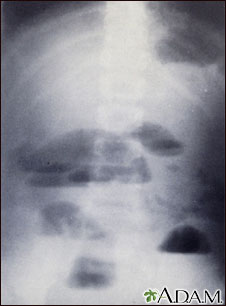

X-rays of the abdomen are important in diagnosing the presence of small bowel obstruction. When obstruction occurs, both fluid and gas collect in the intestine. They produce a characteristic pattern called "air-fluid levels". The air rises above the fluid and there is a flat surface at the "air-fluid" interface.